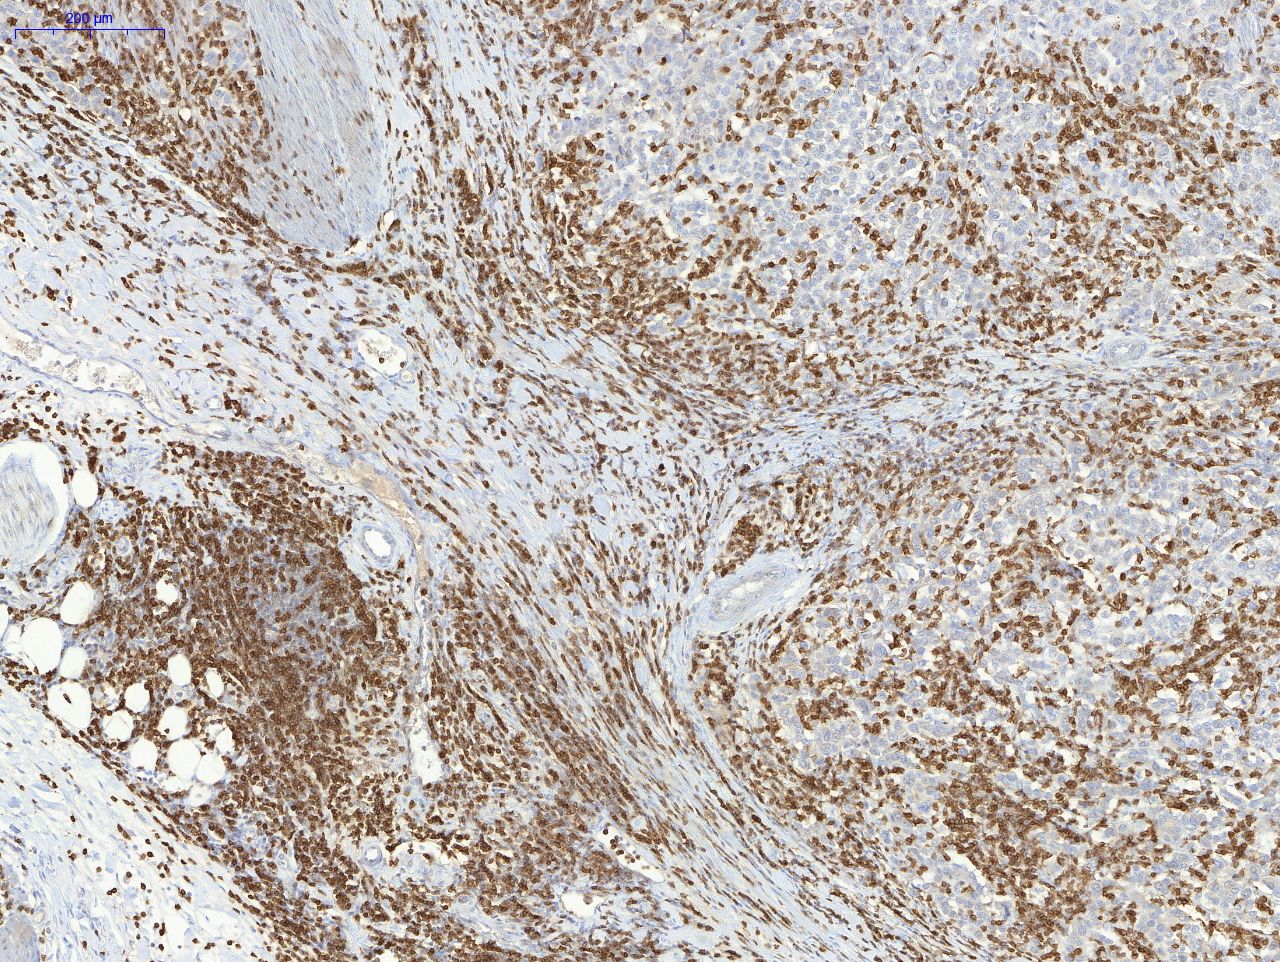

Die Forscher haben nun herausgefunden, dass der Therapieerfolg und das Überleben dieser Patienten durch die Bestimmung der weißen Blutkörperchen, die als stromale tumorinfiltrierenden Lymphozyten (sTIL) bezeichnet werden, vorhergesagt werden können. Diese Lymphozyten werden dabei als einfacher morphologischer Parameter und als Biomarker eingesetzt: Ihre Menge und räumliche Verteilung innerhalb des Tumor-Immun-Milieus erlauben Prognosen über die Stadien der Tumorentzündung und Tumorsubtypen und helfen bei der Personalisierung der Patiententherapie. In weiteren Studien wollen sie ihre Ergebnisse nun überprüfen und die Methode weiterentwickeln.